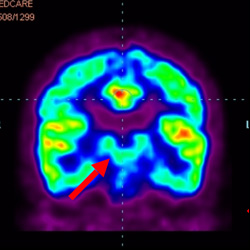

細(xì)胞治療后,藍(lán)色和黑色區(qū)域減少,并且看到更活躍的區(qū)域。這表明損傷減少并改善了大腦功能。

這證明細(xì)胞療法是治療腦癱兒童安全有效的方法。細(xì)胞療法可以更新大腦損傷的核心,并且可以通過 PET CT 掃描來監(jiān)測大腦的改善情況。這些細(xì)胞療法與標(biāo)準(zhǔn)治療一起促進(jìn)腦癱兒童的生長和改善。